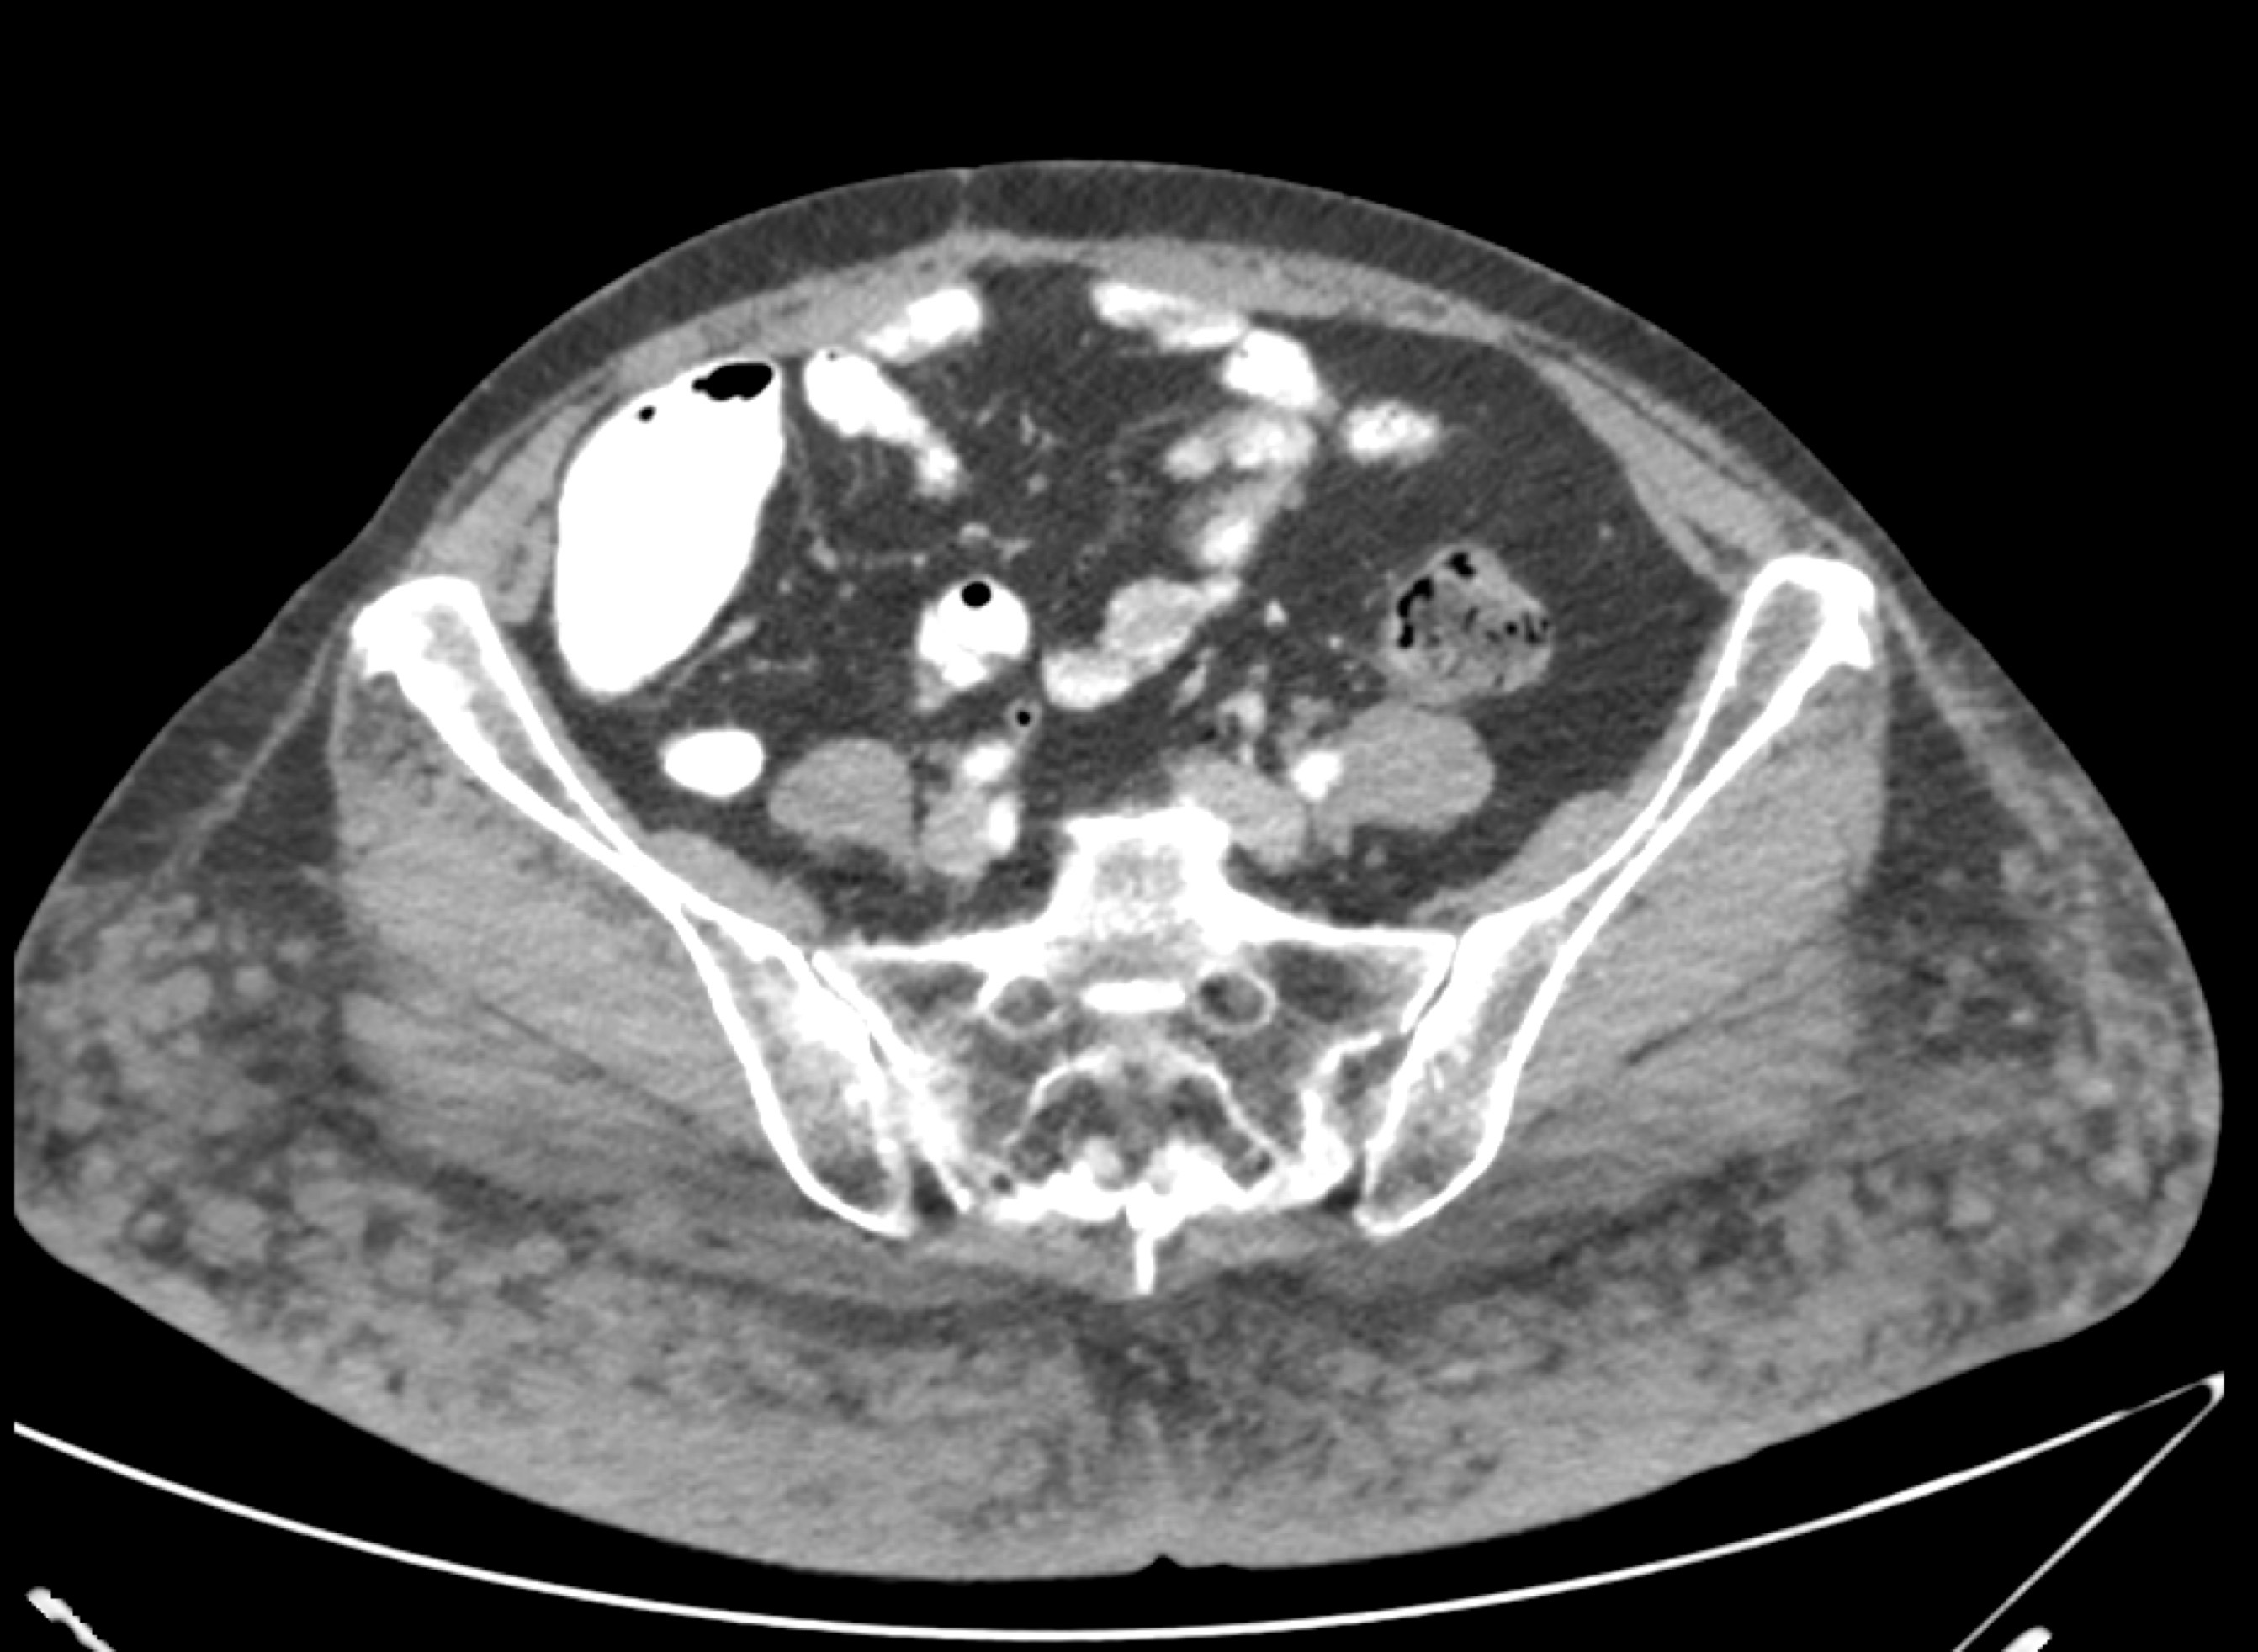

2) The best diagnosis in this case of an incidental finding is?

flow related change

thrombus off aortic valve

papillary fibroelastoma

foreign body